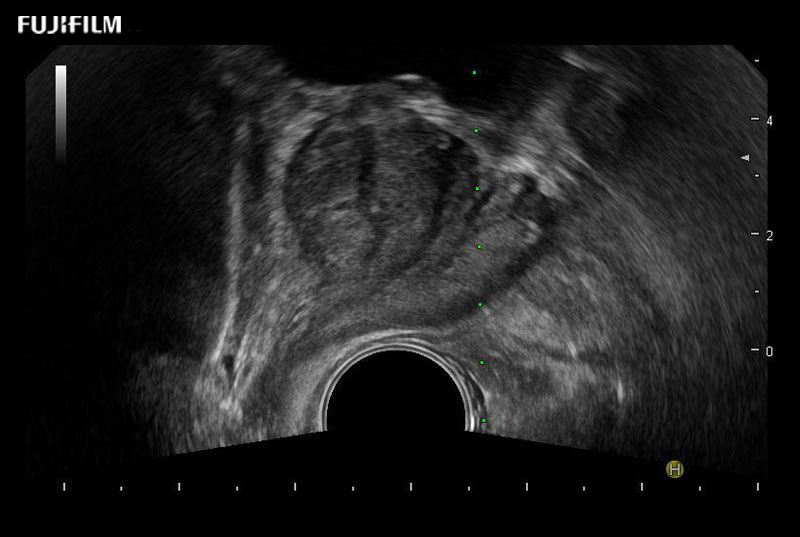

Exclusive 200° FOV end-fire prostate biopsy transducer.

Main Specifications:

Provides real-time imaging of both the sagittal and transverse planes